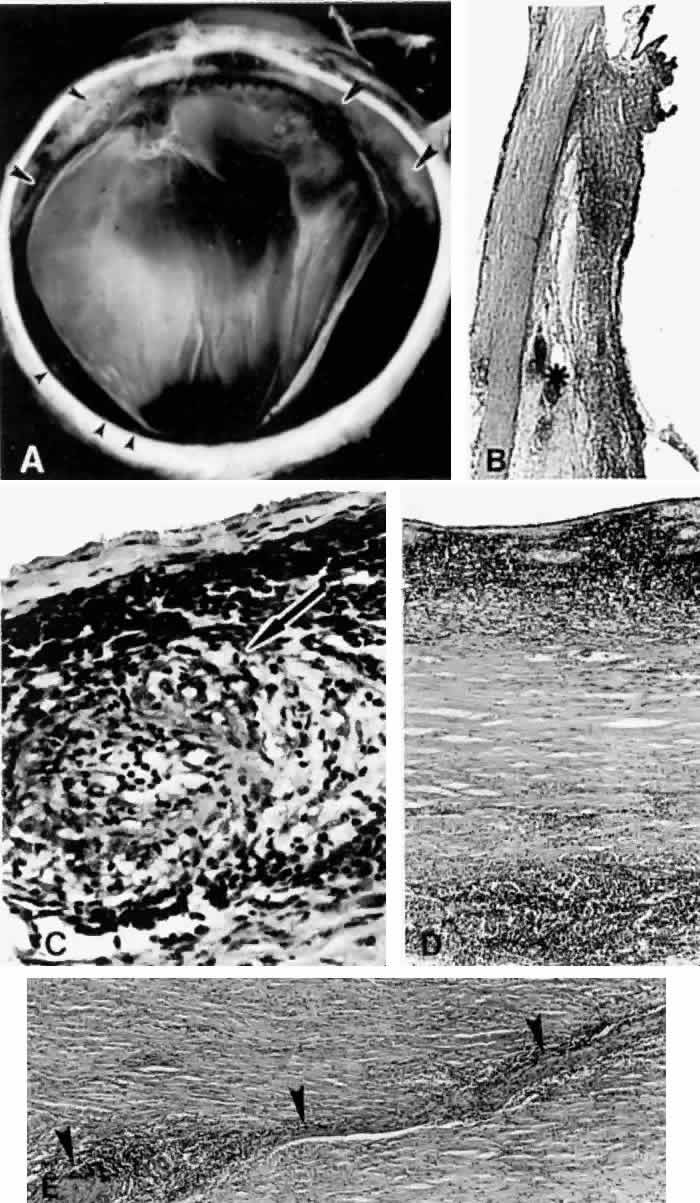

Various uveitides,60–63 including syphilitic uveitis,64 sympathetic ophthalmia (Fig. 12),65–67 toxoplasmosis (Fig. 13),65 rheumatoid arthritis,68 pars planitis,69,70 and Vogt-Koyanagi-Harada syndrome,71 may be associated with the collection of suprachoroidal fluid. In Vogt-Koyanagi-Harada syndrome, a diffuse, bilateral uveitis may lead to an exudative choroidal effusion and secondary nonrhegmatogenous retinal detachment. In addition to associated extraocular clinical features (e.g., vitiligo, poliosis, dysacousia), the presence of pleocytosis in the cerebrospinal fluid (CSF) may help differentiate Vogt-Koyanagi-Harada syndrome from uveal effusion syndrome, which characteristically lacks pleocytosis.

Fig. 12. A ciliochoroidal effusion in the eye of a 16-year-old boy, who developed sympathetic uveitis after a corneal laceration. A. Scar of the traumatic corneal perforation, with fibrous tissue ingrowth (asterisk) and adherent lens remnants (arrowhead) (H & E, × 18). B. The appearance of a ciliochoroidal effusion (asterisk) that was first observed in the eye 2 months after corneal perforation and before the development of uveitis in the fellow eye (H & E, × 96). C. The choroid posteriorly is greatly thickened by intense lymphocytic infiltration in which foci of epithelioid cells (arrowheads) display pigment phagocytosis in the absence of necrosis (H & E, × 185).

Fig. 13. A. A ciliochoroidal effusion (asterisk) associated with Toxoplasma retinochoroiditis (H & E, × 50). B. The retina temporally is totally necrotic with encysted T. gondii (H & E, × 25). C. An old chorioretinal scar (arrow) posterior to the area of necrotic retina (H & E, × 160). D. Intense vasculitis and perivascular lymphocytic infiltration of the central vessels in the optic nerve head (H & E, × 185).

A subconjunctival abscess,72 orbital pseudotumor,73 episcleritis,74–76 scleritis (Fig. 14),9,19,20,65,68,77,78 and vasculitides (Figs. 15 and 16)79–81 such as Wegener's granulomatosis79 (see Fig. 16), polyarteritis nodosa,80,81 occlusive vasculitis,65 or nonspecific vasculitis (see Fig. 15) can produce suprachoroidal edema even without overt signs of inflammation. Scleritis, however, may sometimes produce choroidal inflammation with secondary vasodilation and serous effusion into the suprachoroidal and subretinal space. An infected scleral buckle may also produce a ciliochoroidal effusion months to years after its placement. Removal of sutures and all implanted material is necessary to promote resolution of the effusion.

Fig. 14. Extensive ciliochoroidal effusion (asterisk) associated with a zonular granulomatous inflammatory infiltration in the episclera (arrowheads) of the eye of a 78-year-old man with rheumatoid arthritis.68 Diffuse, nodular inflammatory infiltrates are present in the markedly edematous ciliary body and choroid. There are several folds of retinal pigment epithelium and inner layers of choroid (arrows) and a flat serous detachment of the retina (H & E, × 40).

Fig. 15. A spontaneous ciliochoroidal effusion was mistaken for a malignant melanoma in a 61-year-old woman who presented with pain, blurred vision, keratitic precipitates, and aqueous cells and flare. A. Gross appearance of the ciliochoroidal effusion (large arrowheads). Small whitish inflammatory nodules are present in the choroid (small arrowheads). The apparent retinal detachment is artifact. B. An extensive ciliochoroidal effusion (asterisk) with a moderately intense chronic inflammatory cellular infiltration. (H & E, × 20). C. The choroid viewed posteriorly, showing occlusive granulomatous vasculitis (arrow) and an intense lymphocytic infiltration crowding the choriocapillaris. The retinal pigment epithelium is intact (H & E, × 290). D. Intense lymphocytic infiltration of choroid, inner scleral lamellae, and episclera (H & E, × 55). E. Diffuse scleritis viewed posteriorly, showing perineural lymphocytic infiltration in the episclera and within a scleral canal (arrowheads) (H & E, × 55).

Fig. 16. Peripheral marginal corneal degeneration and conjunctival ulceration developed in a 61-year-old woman with Wegener's granulomatosis.79 Ciliochoroidal effusion (asterisks) was not a clinical problem, but was found on autopsy examination in association with an occlusive vasculitis with fibrinoid necrosis of the anterior and long ciliary arteries. Intense episcleritis is evident (arrow) (H & E, × 55).